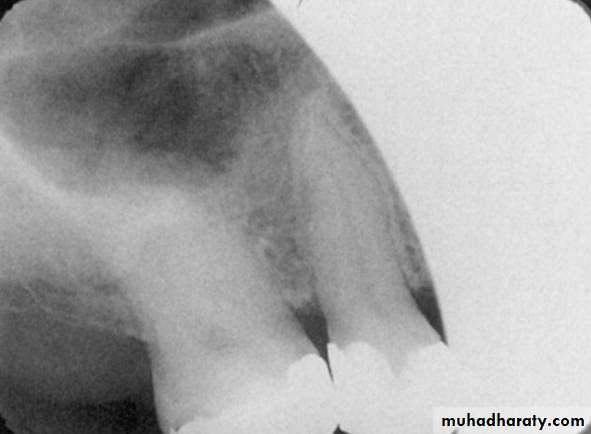

This radiograph demonstrates a cone cut.